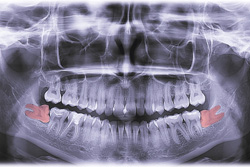

Over the course of human history, our species has changed, and features that once were essential to our survival have become superfluous. At one point, the appendix must have performed some task or function, but researchers still aren’t sure what. Likewise, humans used to need extra teeth! Did you know that most—but not all—people still develop three sets of molars? The final set typically arrives between a person’s late teenage years and their early 20s—a phase in life when people are considered to transition from kids to adults.

Although our ancient ancestors often needed this third set of molars to replace lost teeth early on and to help with chewing tougher foods, modern diets and smaller mouths make wisdom teeth unnecessary. In fact, because of better oral hygiene and shrinking oral cavity sizes, they can even put the rest of your smile at a much higher risk of damage, infection, alignment shifting, and pain. When your mouth is unable to make space for them, removing wisdom teeth before they start to cause harm preserves your teeth for the rest of your adult life.